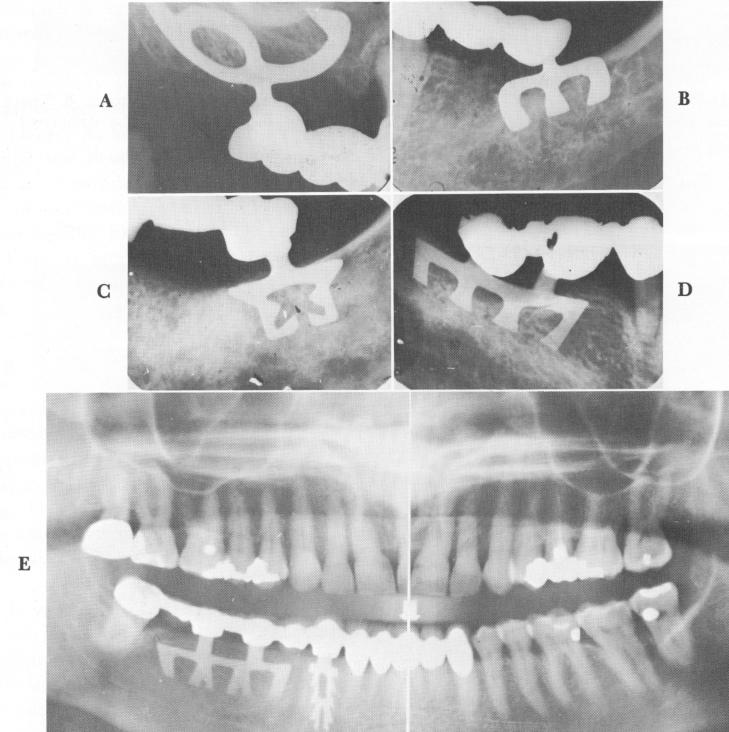

Fig. 11-22. A to D, For dense bone the apical end of the blade should be open. E, A Panorex showing open-ended blades for dense and deep bone.

Fig. 11-21. Horizontal and vertical set screws inside the posts may give added stability in affixing the prosthesis. (Courtesy Park Dental Research Corporation.)